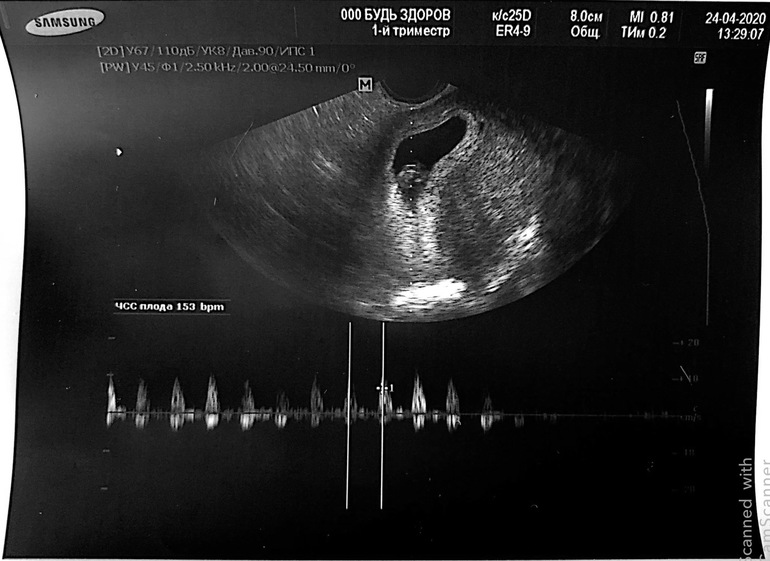

Сердцебиение - 153 уд в минуту;

Когда мне включили сердцебиение , я прослезилась. Не ожидала от себя...

Какой же это все-таки волнительный момент..